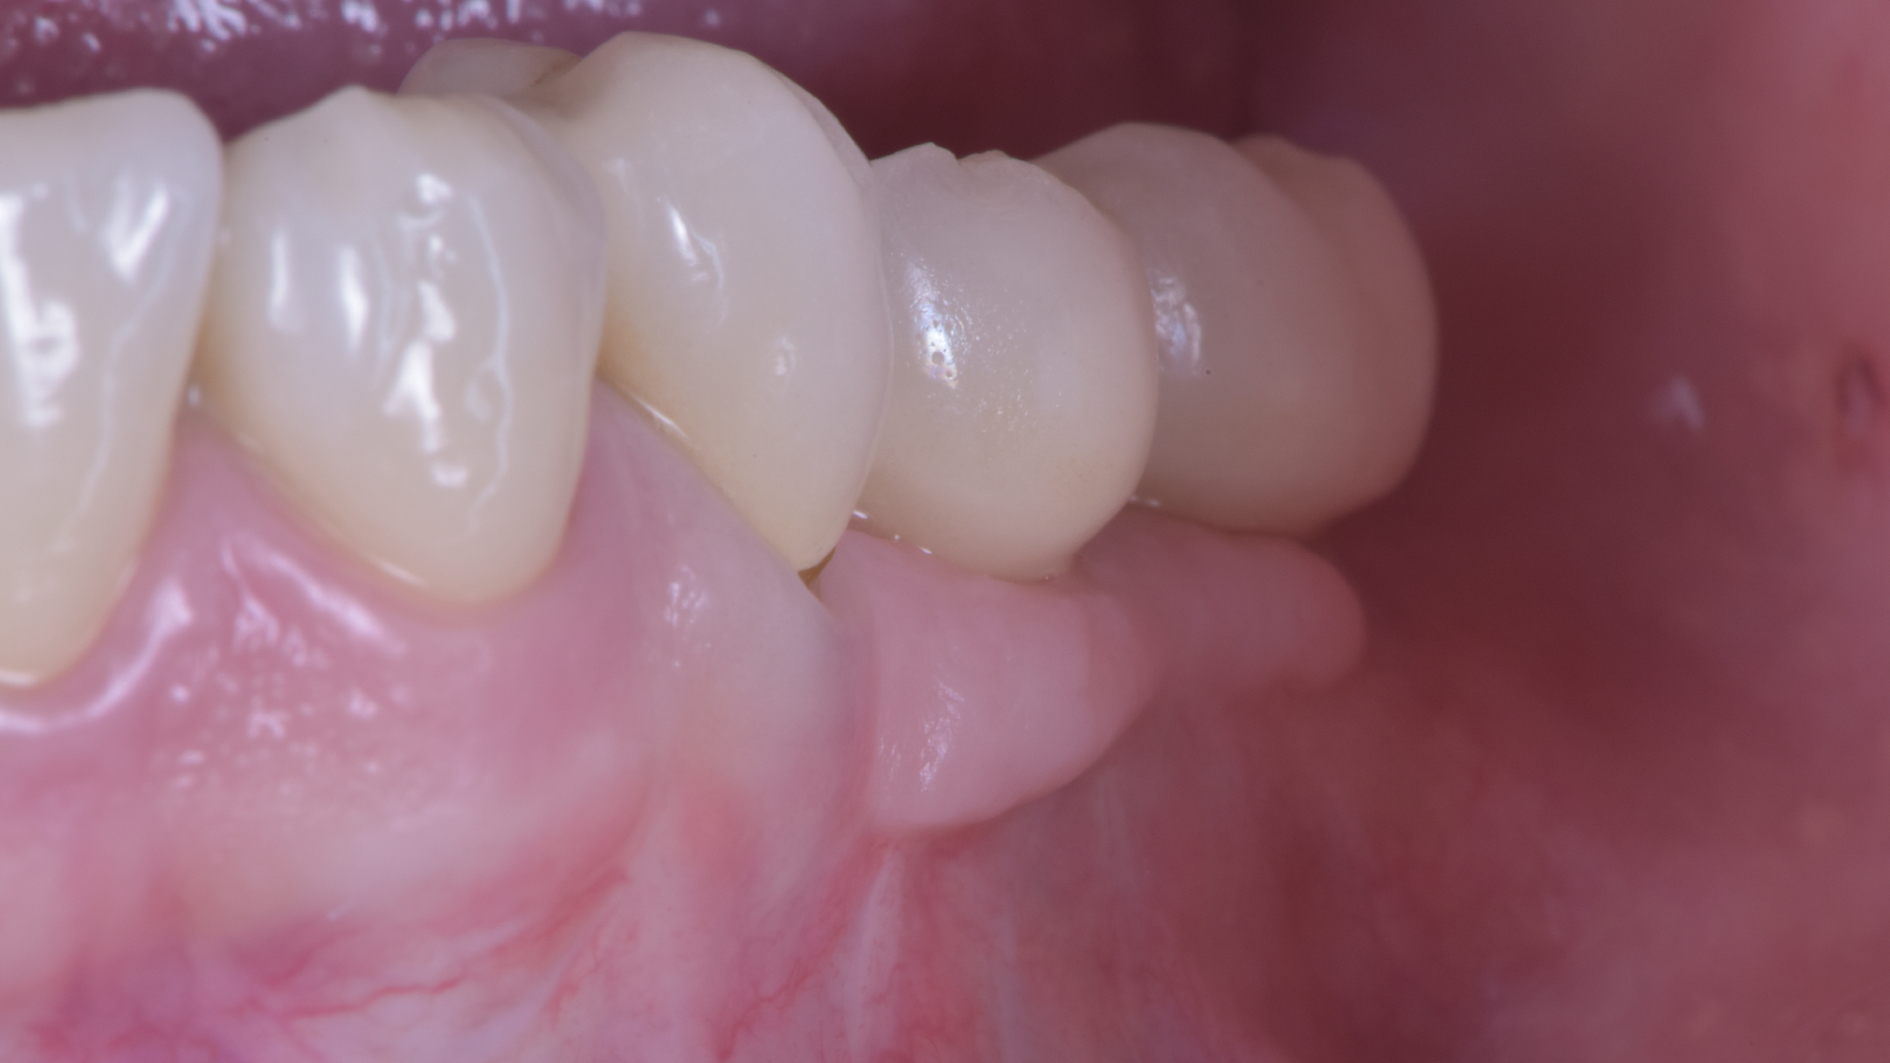

Prendiamo un caso quotidiano. Quello di Alessia che ha 33 anni:

Puoi buttare giù due viti e metterci sopra due denti facendo una cosa molto lontana dalla natura.

O puoi riabilitare la paziente adeguatamente:

Ma per fare questo non ci sono polverine magiche di osso di dinosauro o impianti di un millimetro. Ci sono anni di studio, sudore e sangue (E SGUARONE!!) per noi… e un VAS 2 per la paziente!!!!!!! ?